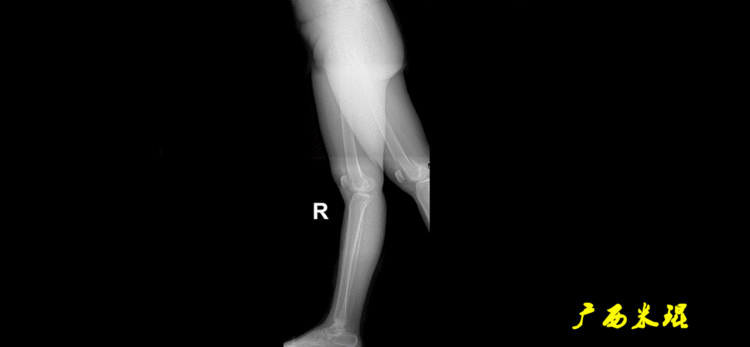

下肢力线及相关角度测量的前提是必须拍摄标准的站立位也就是负重位的下肢全长片。目前这样的照片都是放射科的技师在电脑上拼接出来的,大部分医院的DR都能够做到这一点。

患者直立于摄影架上,后背贴近摄影架,双手自然下垂,膝关节尽量伸直,足部与双肩同宽,要求投照时双髌骨朝正前方,通常患者双足尖应平行向前即可。

提醒一下大家,拍摄过程中应避免下肢的外旋和内旋。如果有一侧肢体短缩时,投照应当用脚垫垫高短缩肢体,使骨盆保持水平,这样下肢短缩测量才精确。如果有肢体旋转畸形时,还是以髌骨朝前为标准,虽然此时双足可能不能保持平行。

二、下肢全长片的基本要求

无论如何,拍摄出来的下肢全长片必须包含髋关节中心、膝关节中心及踝关节中心,否则对临床是无用的。有了一张下肢的全长照片,我们需要确定下肢关节的中心点,通过中心点画出下肢的各种轴线,然后利用轴线与关节线的相交得出各种所需要的角度。